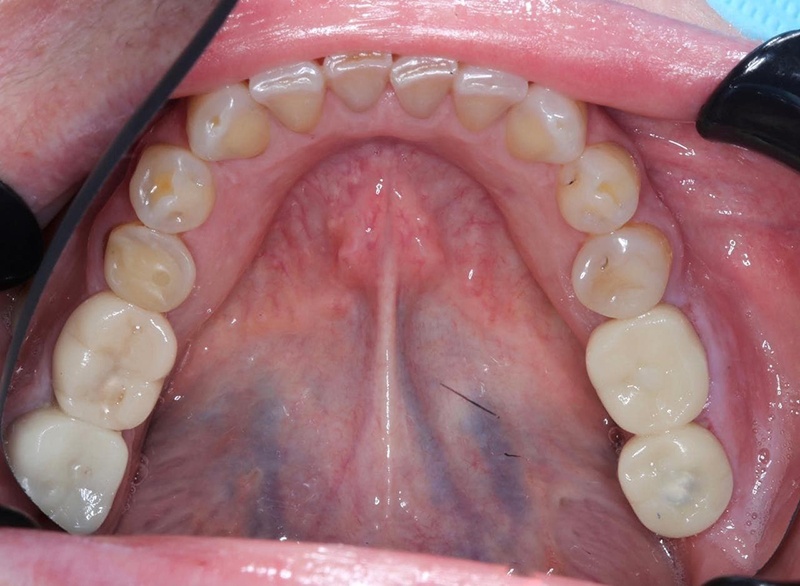

С чем пришла пациентка — нижняя челюсть

Что у нас было на входе? С правой стороны когда-то были удалены шестой и седьмой зубы, восьмой съехал на место седьмого. С левой — удалён шестой, седьмой с не очень удачно пролеченными каналами, в восьмом огромная полость. Шестой был удалён так давно, что седьмой практически полностью теперь на его месте. Восьмой лежит, не прорезавшийся. Тёмное пятно вокруг седьмого ничего хорошего не говорит, за корнем какая-то проблема локализуется.

Установленные временные коронки. Объект на шестом зубе легко принять за кариес, но на самом деле это шахта винта, который держит временную коронку на импланте. В общем, зуб выглядит сейчас страшненько, но это живое фото в процессе лечения. Новых фото, где он уже совсем здоровый и красивый, пока ещё нет. Кстати, если бы кариес на этом зубе был, то есть когда у нас не тотальная реставрация зубов, а какие-то небольшие полости, мы бы лечение не задваивали, а устраняли бы дефекты уже во время финальной реставрации. При тотальной реставрации мы бы всё зачистили заранее.